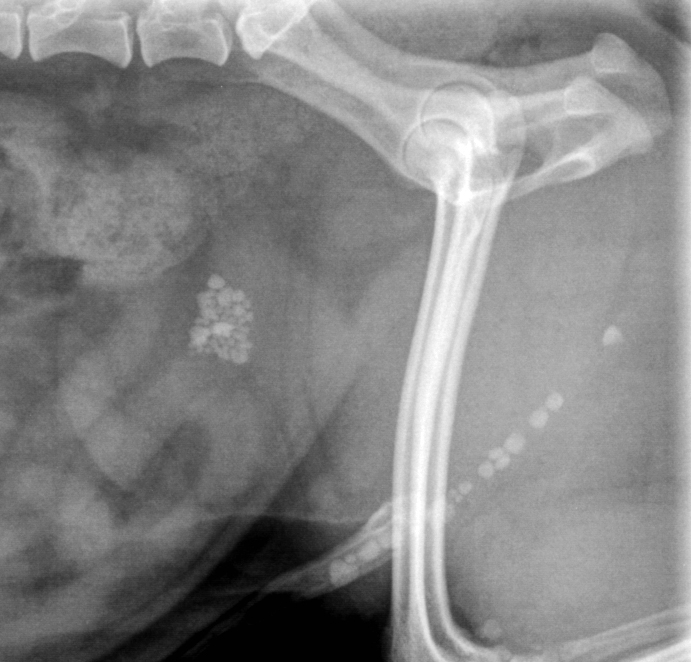

• Identifier les principales interventions chirurgicales concernant les reins, les uretères, la vessie et l’urètre, et en connaître les indications.

• Connaître les indications et les techniques d’urétrostomie chez le chat et le chien.

• Indications et techniques d’urétrostomie chez le chat

• Indications et techniques d’urétrostomie chez le chien

• Urétrostomie périnéale chez le chat

• Urétrostomie trans-pelvienne chez le chat

• Urétrostomie scrotale chez le chien